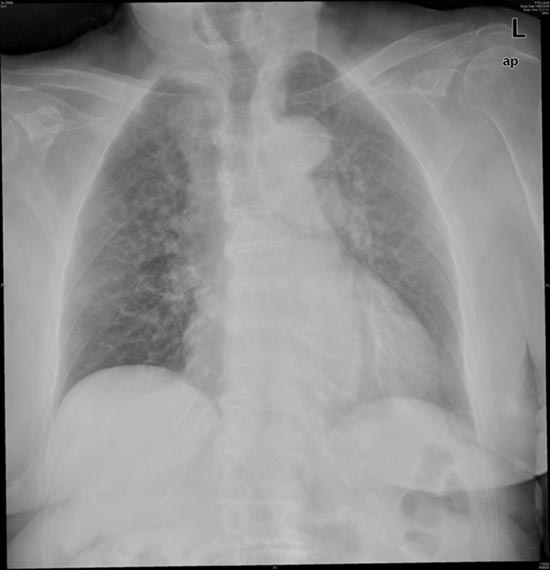

Fibrosis pulmonar. ICC.